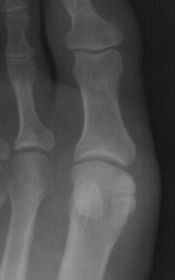

| Describe the alignment of metatarsal 2 | There is no angulation nor displacement of the distal segment relative to the proximal segment. |

| Describe the alignment of metatarsal 3 | The distal segment is displaced laterally (50% apposition) and angulated medially. |

| Describe the alignment of metatarsal 4 | The distal segment is displaced laterally (75% apposition) but there is no apparent angulation. |

| Describe the tubulation of the metatarsals | Metatarsals are overtubulated - decreased girth. |

| Describe the tubulation of the metatarsals | Metatarsals are undertubulated - increased girth. |